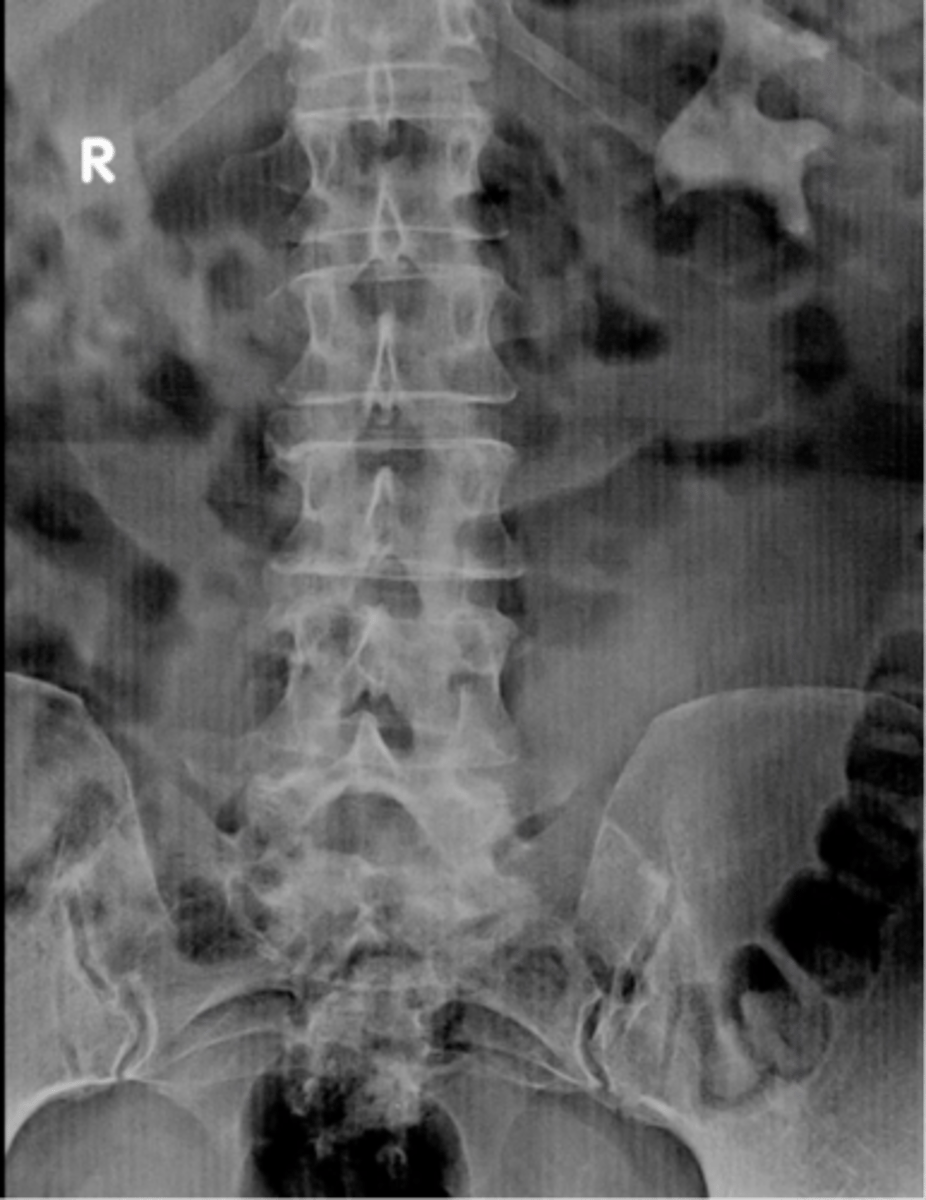

Normal prone AXR

Normal AXR (and normal size liver)

Normal AXR (and normal organs)

Normal AXR (and normal structures)